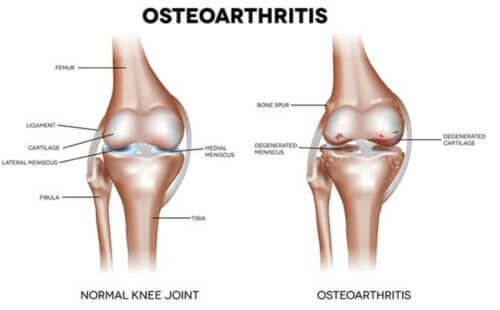

이 글에서는 고관절 골관절염의 특징과 증상에 대해 알아보려고 한다. 고관절 골관절염은 관절의 끝부분마다 존재하는 유리 연골이 마모된 상태이다. 이러한 연골은 관절을 감싸 다른 관절과 마찰하지 않도록 보호하고 하중의 영향을 줄인다.

외상, 유전적 결손, 관절 오용으로 인한 불균형은 연골의 수분 보유 능력 저하를 유발한다. 그 결과 뼈가 변형될 때까지 관절이 서서히 마모되면서 통증과 이동성 상실이 발생한다.